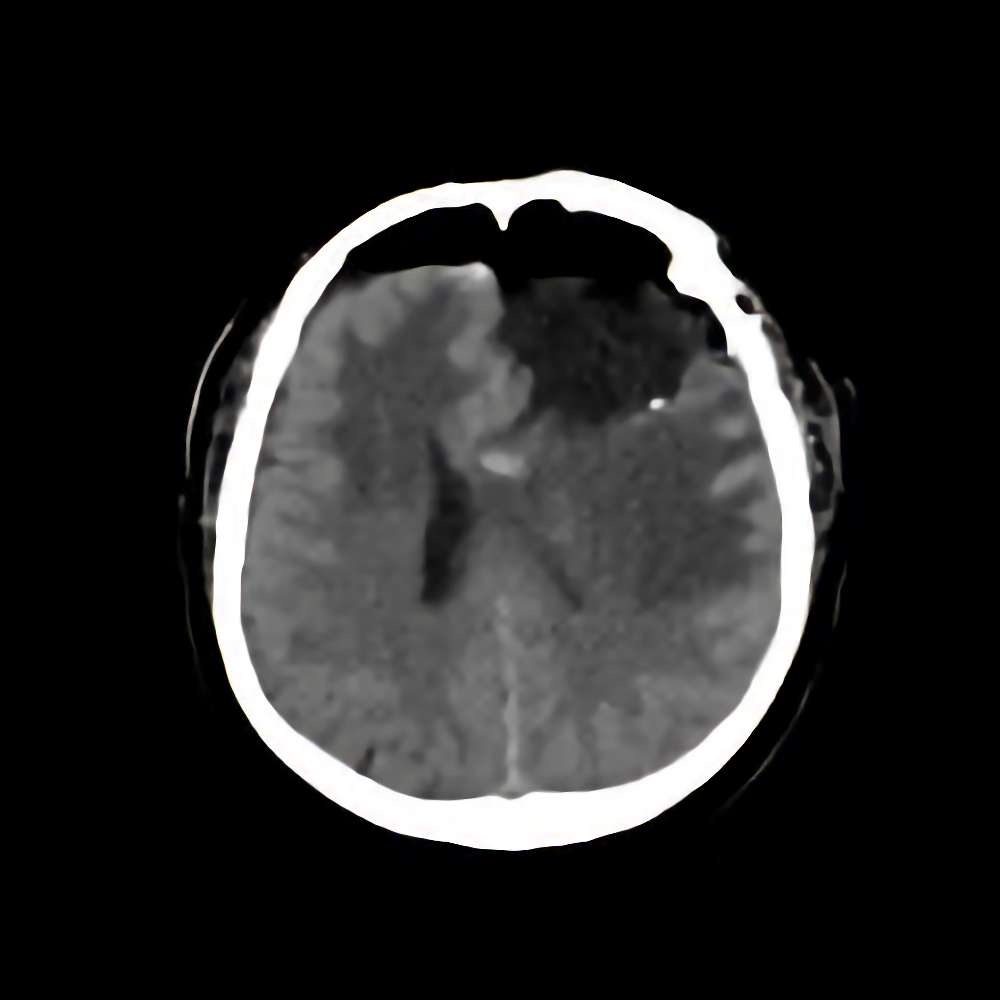

脳腫瘍 手術実績

症例 '16年2月

No.

※ 画像をクリックすると拡大表示します。症例No.は平成29年から起算しています。

年_番号

手術年月

患者年齢

’16_9

'16年2月

60代

病名

術式

備考

脳腫瘍

断層撮影

手術前

1

手術前2

手術後